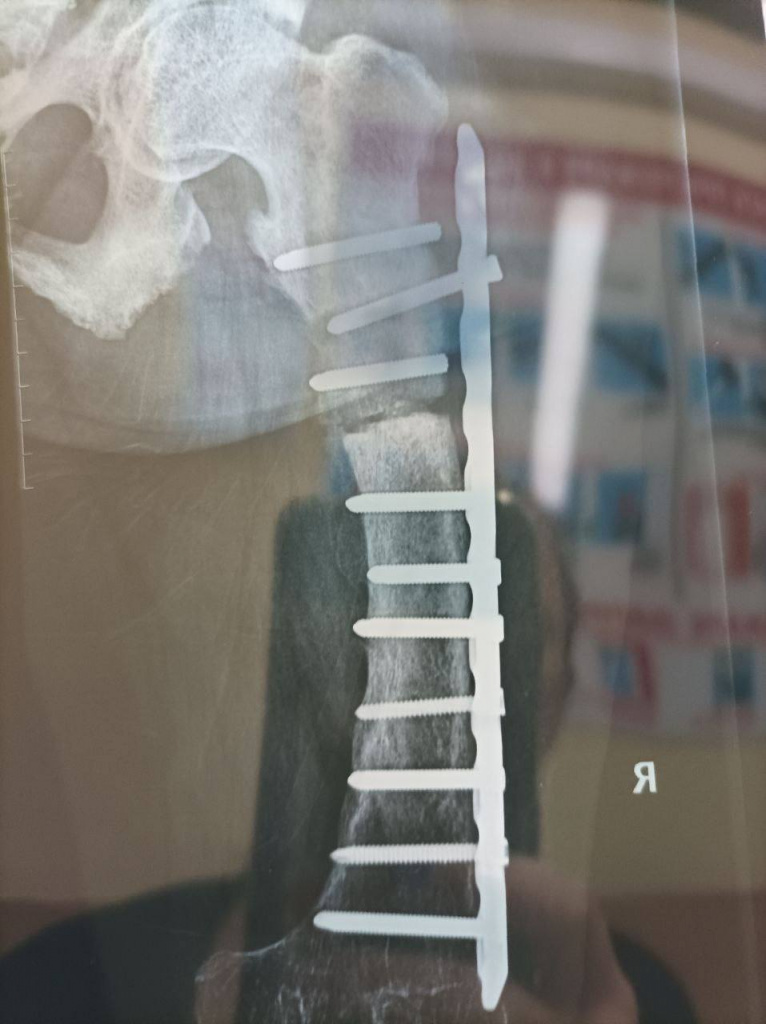

Кристине 38 лет, она страдает от генетического заболевания, из-за которого у нее не срастаются кости. Женщина испытывает сильные боли и с трудом передвигается. По ее словам, муж всегда заботился о ней, поэтому она не видела острой необходимости в оформлении второй группы инвалидности. Однако в октябре ее 36-летнего мужа Андрея мобилизовал Петровский военкомат.

Сообщается, что незадолго до объявления частичной мобилизации врачи сообщили девушке о необходимости операции, поскольку болты в ее ноге сломались.